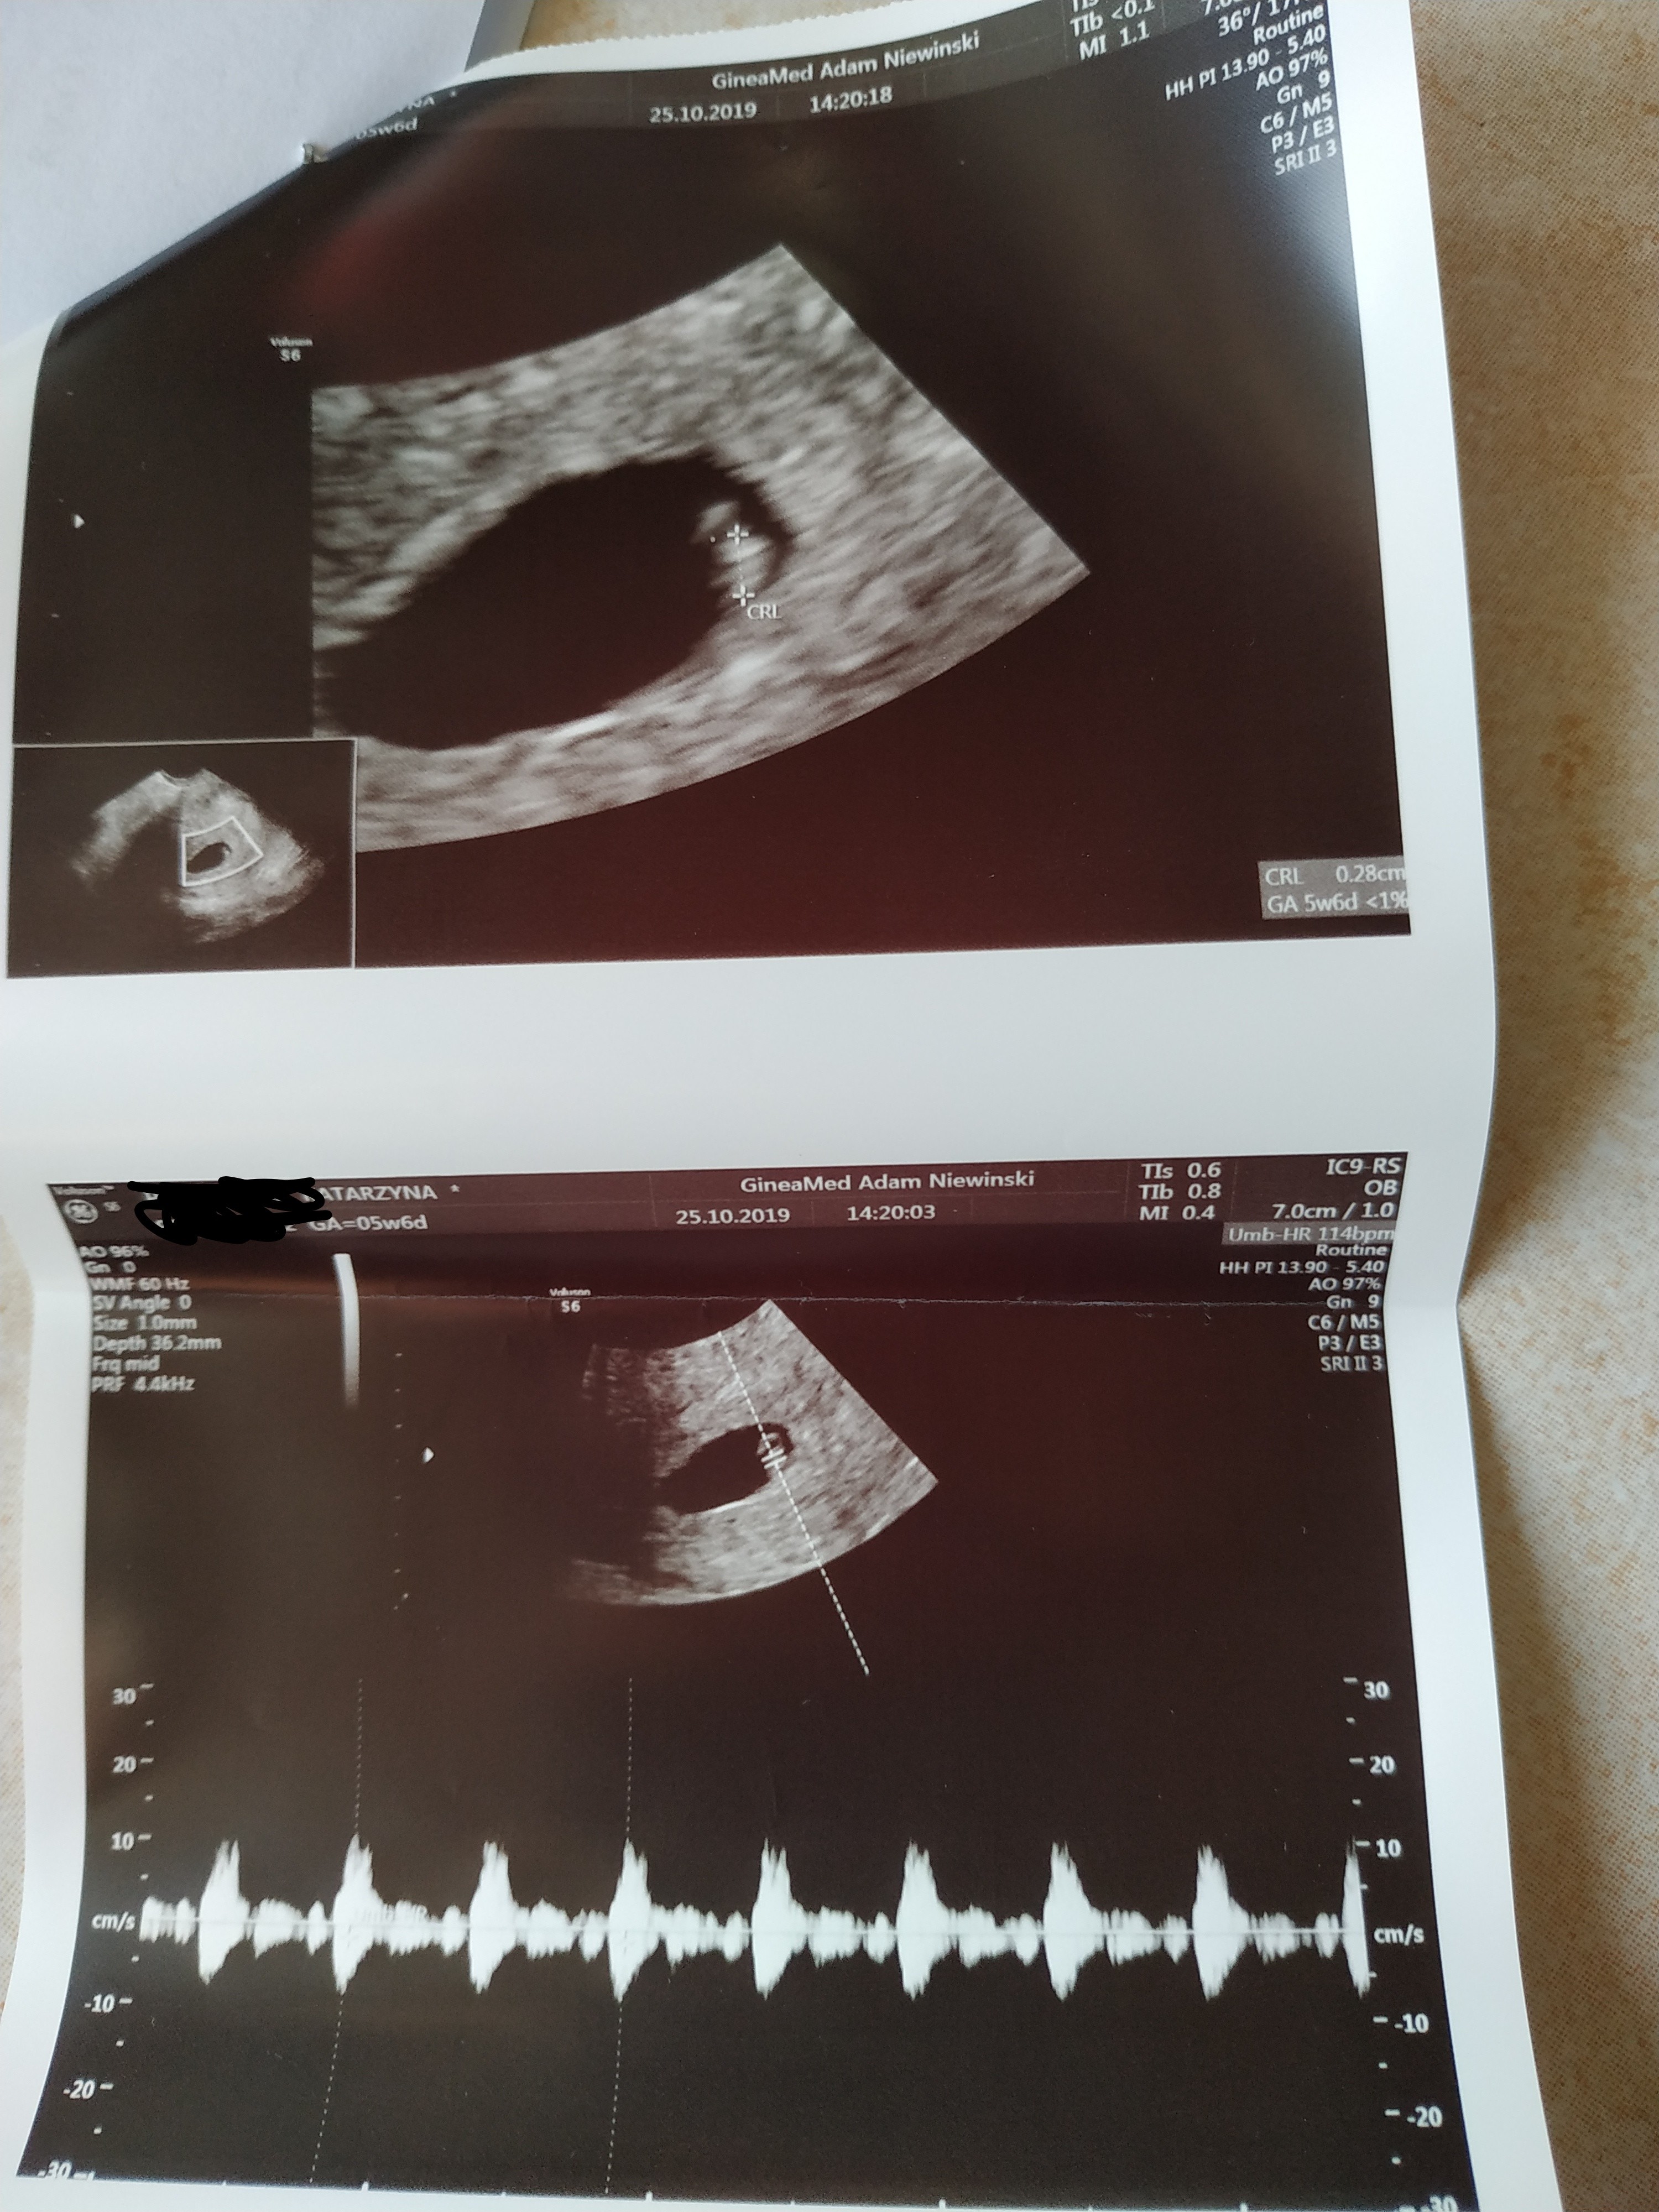

Ja znów po wizyciewidziałam piękne 2 cm dziecko

z USG 8+2 dni

serduszko pięknie pracuje. Jak dotąd wszystko dobrze. Pozdrawiam Was